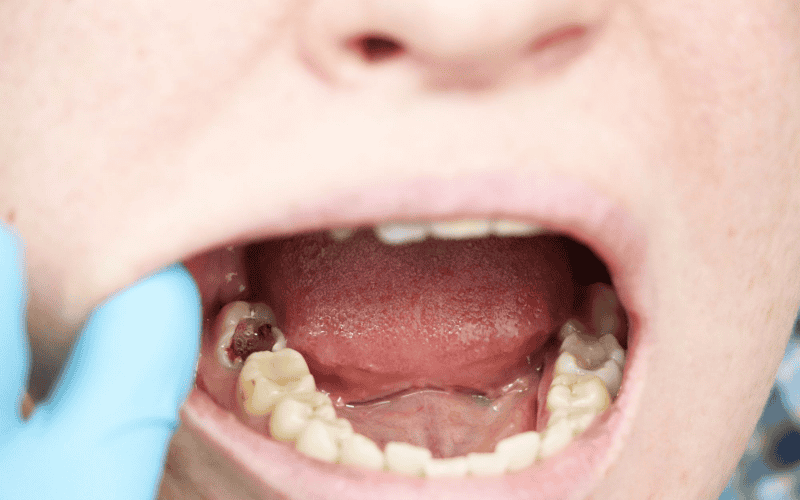

Las caries dentales suelen considerarse un problema menor de salud, asociado principalmente al dolor o a la pérdida de una pieza dental. Sin embargo, cuando no se tratan de manera oportuna, pueden derivar en complicaciones graves que, en casos excepcionales, ponen en riesgo la vida. Aunque no es común, la evidencia médica confirma que una caries avanzada puede desencadenar consecuencias potencialmente mortales.

Las caries se producen cuando las bacterias presentes en la boca descomponen los azúcares de los alimentos y generan ácidos que dañan el esmalte dental. Si el daño progresa y alcanza la pulpa del diente, donde se encuentran los nervios y vasos sanguíneos, puede originarse una infección conocida como absceso dental. En este punto, el problema deja de ser local y puede extenderse a otras zonas del cuerpo.